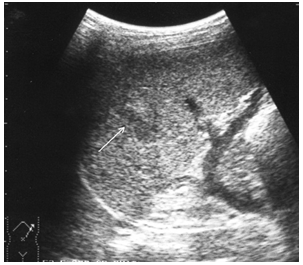

Пренатальная диагностика. Во время плановых ультразвуковых исследований (УЗИ) во втором или третьем триместре беременности врач может заметить косвенные признаки кишечной непроходимости у плода. К ним относятся расширенные петли кишечника и так называемый «гиперэхогенный кишечник», когда его ткани на УЗИ выглядят более яркими, чем обычно. Такие находки не являются стопроцентным подтверждением диагноза «мекониальный илеус», но требуют более пристального наблюдения.